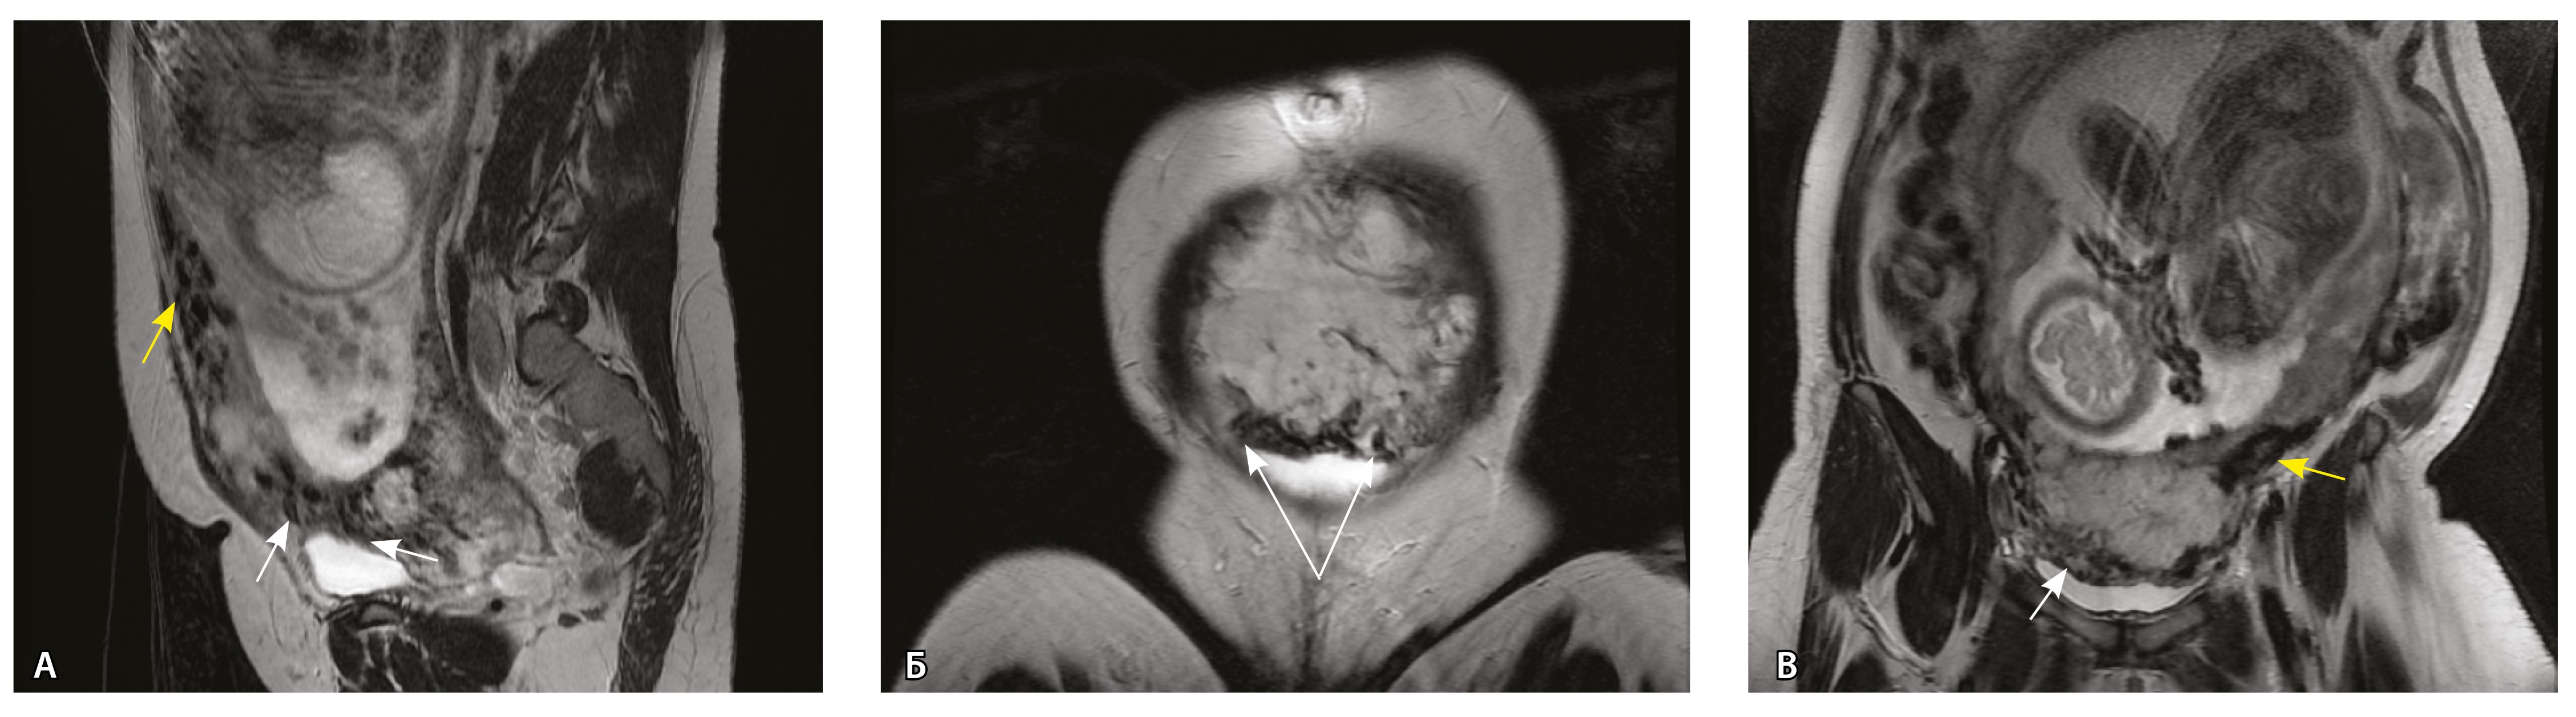

Сосуды 5-го типа. Наличие гиперваскуляризации за пределами матки по данным МРТ, на границе с мочевым пузырем с вовлечением его стенки, сосуды в области перешейка матки, параметрия, в том числе в сочетании с признаками фиброза, наличием рубцово-спаечных изменений и др. Можно предположить, что сосуды 5-го типа являются аналогом pl. рercreta PAS 3b, 3c (рис. 15).

Рис. 15. Беременность 34 недели, pl. percreta, PAS 3b по FIGO (A, Б), PAS 3c по FIGO (В). На магнитно-резонансных томограммах в режиме Т2-взвешенного изображения в сагиттальной (A, В) и аксиальной (Б) плоскостях определяется гиперваскуляризация в области выраженно истонченного нижнего маточного сегмента с распространением сосудов на заднюю стенку мочевого пузыря в области дна (белые стрелки), в область перешейка матки (желтые стрелки)

Данный вариант в патоморфологической картине наиболее сложен для оценки ввиду того, что такие структуры, как параметрий, перешеек матки, стенка мочевого пузыря, обычно не предоставляются в виде макропрепаратов, поэтому визуальные методы, в частности МРТ, могут с большей точностью оценить вовлеченность смежных структур. На микропрепаратах данный вариант инвазии плаценты сочетается с рубцово-спаечными изменениями задней стенки мочевого пузыря с нижним маточным сегментом (рис. 16).

Рис. 16. Гистологическое исследование маточно-плацентарного сегмента при pl. percreta, определенной по данным магнитно-резонансной томографии. Окраска пикрофуксином по Маллори (красный цвет – мышечные волокна, голубой – соединительная ткань). Стенка мочевого пузыря плотно сращена с истонченным маточным сегментом, характеризуется наличием кровеносных сосудов (синяя стрелка). Фиброз задней стенки мочевого пузыря, разобщенные мышечные пучки, замурованные в соединительную ткань (поле отмечено пунктиром). Инвазия ворсин плаценты в бухты миометрия (помечена черным треугольником). Слизистая мочевого пузыря показана стрелкой. Ретроплацентарная гематома помечена звездочкой. Коллаж из 12 фото при увеличении × 100

Тип 5. Наличие гиперваскуляризации за пределами матки: на границе с мочевым пузырем, перешейком матки, параметрием, в том числе с признаками фиброза (характерно для pl. рercreta различных степеней – PAS 3b, 3c по FIGO).

Сосуды 5-го типа определялись только у пациенток с pl. percreta (77,8%) по данным МРТ (PAS 3b, 3c по FIGO). Визуальная картина была обусловлена наличием гиперваскуляризации по поверхности матки в том числе на границе с мочевым пузырем, перешейком матки и параметрием. Нередко подобные изменения сочетались с признаками фиброза. При патоморфологическом исследовании в этой группе пациенток признаком pl. percreta считался рубцово-спаечный процесс с задней стенкой мочевого пузыря, в том числе в сочетании с сосудами 4-го типа, что было обнаружено всего у 2 пациенток. В то же время в литературе рl. percreta описана как редкое проникновение ворсин за пределы серозной оболочки матки в соседние органы (заднюю стенку мочевого пузыря, перешеек матки, параметрий), подтвержденное патоморфологически, хотя представленные случаи достаточно дискутабельны и не имеют четкого патоморфологического подтверждения [21, 22]. В нашем исследовании не удалось обнаружить ворсины хориона за пределами матки в смежных органах ни в одном из наблюдений. По нашему мнению, истонченный нижний маточный сегмент вместе с различного рода гиперваскуляризацией серозной оболочки матки не может быть единственным достоверным признаком pl. percreta, так как в составе стенки определяется атрофичный миометрий с рубцовой тканью и серозная оболочка матки оказывается неповрежденной. При этом такие структуры, как параметрий, перешеек матки, стенка мочевого пузыря, обычно не предоставляются для исследования в виде макропрепаратов, а в процессе операции удаляется лишь часть стенки матки. Ввиду этого сосуды на наружной поверхности матки лучше визуализируются при инструментальных методах исследования, а не при гистологическом исследовании. В ходе оперативного лечения сосуды могут быть повреждены, также они спадаются, меняется их кровенаполнение, поэтому картина МРТ может существенно отличаться от патоморфологической. Тем не менее проведенный нами анализ сосудов стенки матки показал четкую корреляцию между увеличением диаметра и количества сосудов как в миометрии, так и в составе серозного покрова матки с увеличением степени приращения плаценты. Ряд патоморфологов по-прежнему считает pl. percreta мифом. Но в клинической практике и в практике врачей-рентгенологов на основании МР-признаков данный вариант приращения выделяется и занимает важное место. Для наиболее точной диагностики данные патоморфологического исследования, визуальных методов диагностики, в частности МРТ, интраоперационная картина должны быть оценены не по отдельности, а в совокупности [23].